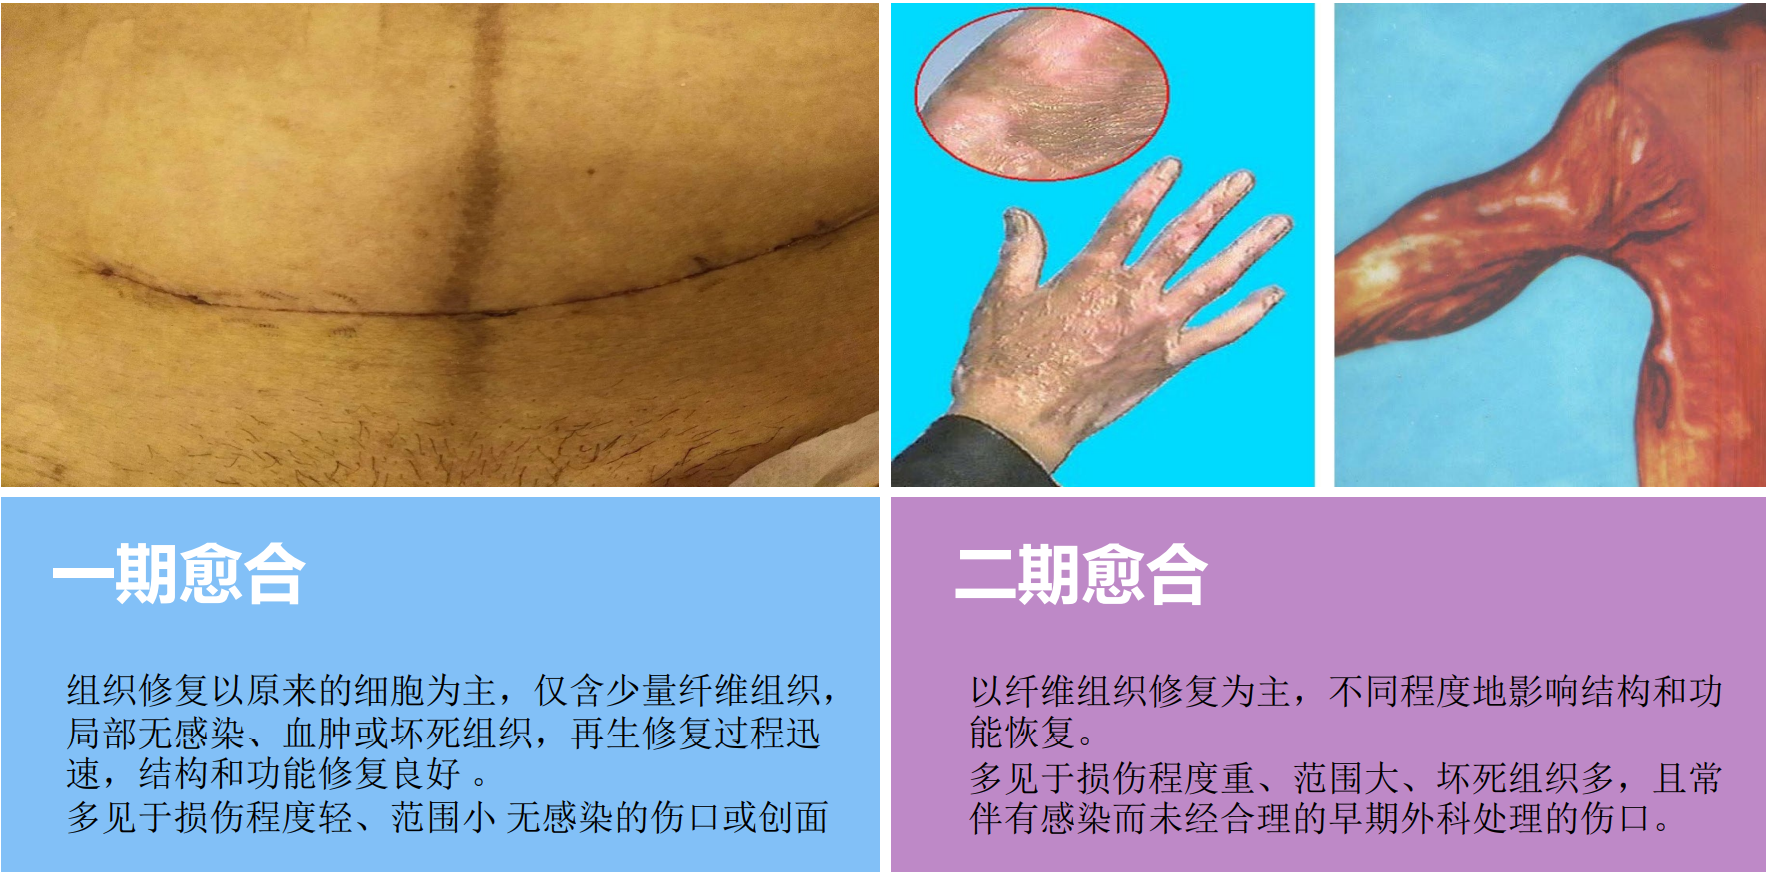

10. 创伤及其处理方式

创伤

外界机械性物体接触或侵袭机体所造成,如锐器造成的切伤和刺伤、钝性物体造成的挫伤和挤压伤。有的创伤是体内结构之间牵张力失衡所造成,如肌肉强烈收缩可造成腰肌、韧带或肌肉本身的损伤。

生活中常见的伤口:划伤(可能会伤害到真皮组织及皮下的脂肪层,甚至更深的组织,出血会很明显)擦伤(深层组织仍是完整的)、咬伤(极易被细菌感染)刺伤(容易发生炎症)

创伤愈合的类型

浅层组织清创术

将污染伤口变成清洁伤口,为组织愈合创造良好条件 清创时间越早越好,伤后 6 ~ 8小时内清创,一般都可达到一期愈合